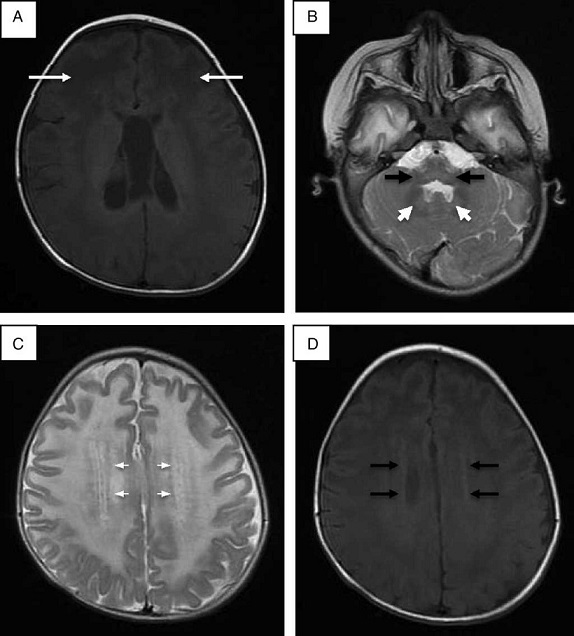

Se realizó punción lumbar, que mostró hiperproteinorraquia; la tomografía de cráneo mostró hipodensidad generalizada de la sustancia blanca. La resonancia magnética (RM) de cráneo corroboró afección de sustancia blanca generalizada, ganglios basales, tálamos, tallo cerebral y cerebelo (Fig. 1). Se descartó enfermedad de Krabbe mediante ensayo enzimático y secuenciación del gen GALC. En la reevaluación del caso a los 20 meses de edad, las alteraciones en la RM hicieron sospechar de enfermedad de Alexander, y la secuenciación del gen GFAP reportó una mutación en el exón 4 c.716G > A, que ocasionó un cambio de arginina por histidina en la posición 239 de la proteína (p.Arg239His).

Figura 1 Resonancia magnética de cráneo. A. Imagen potenciada en proyección axial SE en T1 donde las flechas señalan mayor afección de la sustancia blanca de predominio frontal. B. Alteraciones en la señal de la sustancia blanca del cerebelo, núcleo dentado y bulbo raquídeo en imagen potenciada en FSE T2. C. Halo hiperintenso en proyección axial en FSE T2. D. Halo hipointenso en T1 proyección axial.